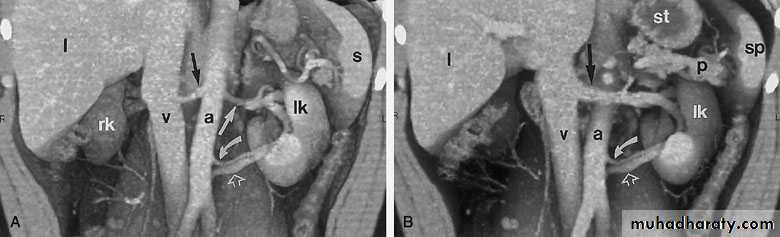

MAGNETIC RESONANCE IMAGING (MRI)Protons within the body can be thought of as small, spinning bar magnets. Hydrogen has a single proton. When a patient is placed in a large magnetic field, the hydrogen protons within the body align, and this alignment leads to the formation of a net magnetic vector within the patient.

Contrast: Gadolinium

No

radiation